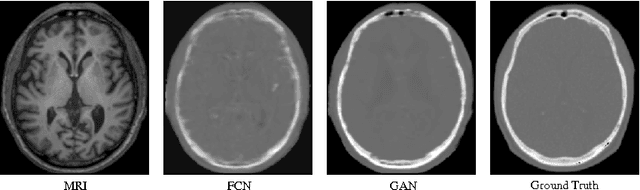

Abstract:Computed tomography (CT) is critical for various clinical applications, e.g., radiotherapy treatment planning and also PET attenuation correction. However, CT exposes radiation during acquisition, which may cause side effects to patients. Compared to CT, magnetic resonance imaging (MRI) is much safer and does not involve any radiations. Therefore, recently, researchers are greatly motivated to estimate CT image from its corresponding MR image of the same subject for the case of radiotherapy planning. In this paper, we propose a data-driven approach to address this challenging problem. Specifically, we train a fully convolutional network to generate CT given an MR image. To better model the nonlinear relationship from MRI to CT and to produce more realistic images, we propose to use the adversarial training strategy and an image gradient difference loss function. We further apply AutoContext Model to implement a context-aware generative adversarial network. Experimental results show that our method is accurate and robust for predicting CT images from MRI images, and also outperforms three state-of-the-art methods under comparison.